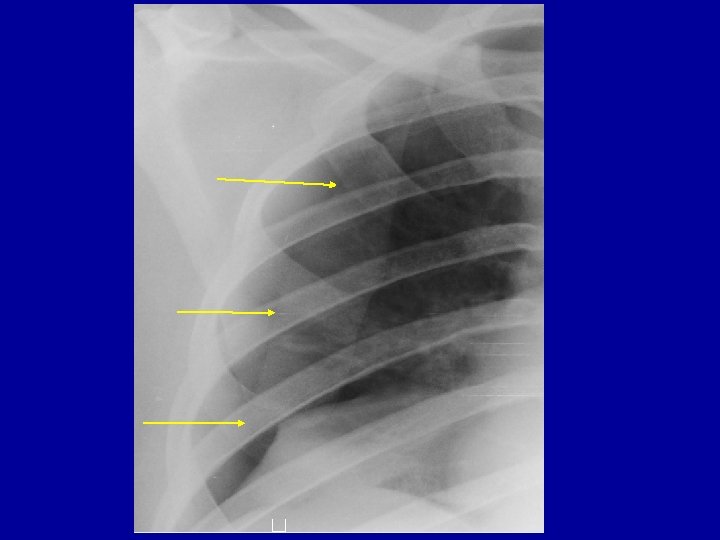

Anticipated problems needing intervention 1. 2. 3. 4. 5. Tension pneumothorax Massive Hemothorax Open Pneumothorax Flail Chest Cardiac Tamponade Treatment – Intercostal drain insertion Sealing of the wound Intubation & ventilation

Diagnose-5 places to look for • • • External Long bones Chest – x ray chest Abdomen - FAST Pelvis and Retro peritoneum Shock in a multiply injured patient is “hemorrhagic shock” unless proved otherwise

Radiology • X rays – – Chest – Pelvis – C Spine – lateral view • FAST • CT ? ? Do Not Shift Hemodynamically unstable patient to Radiology Room